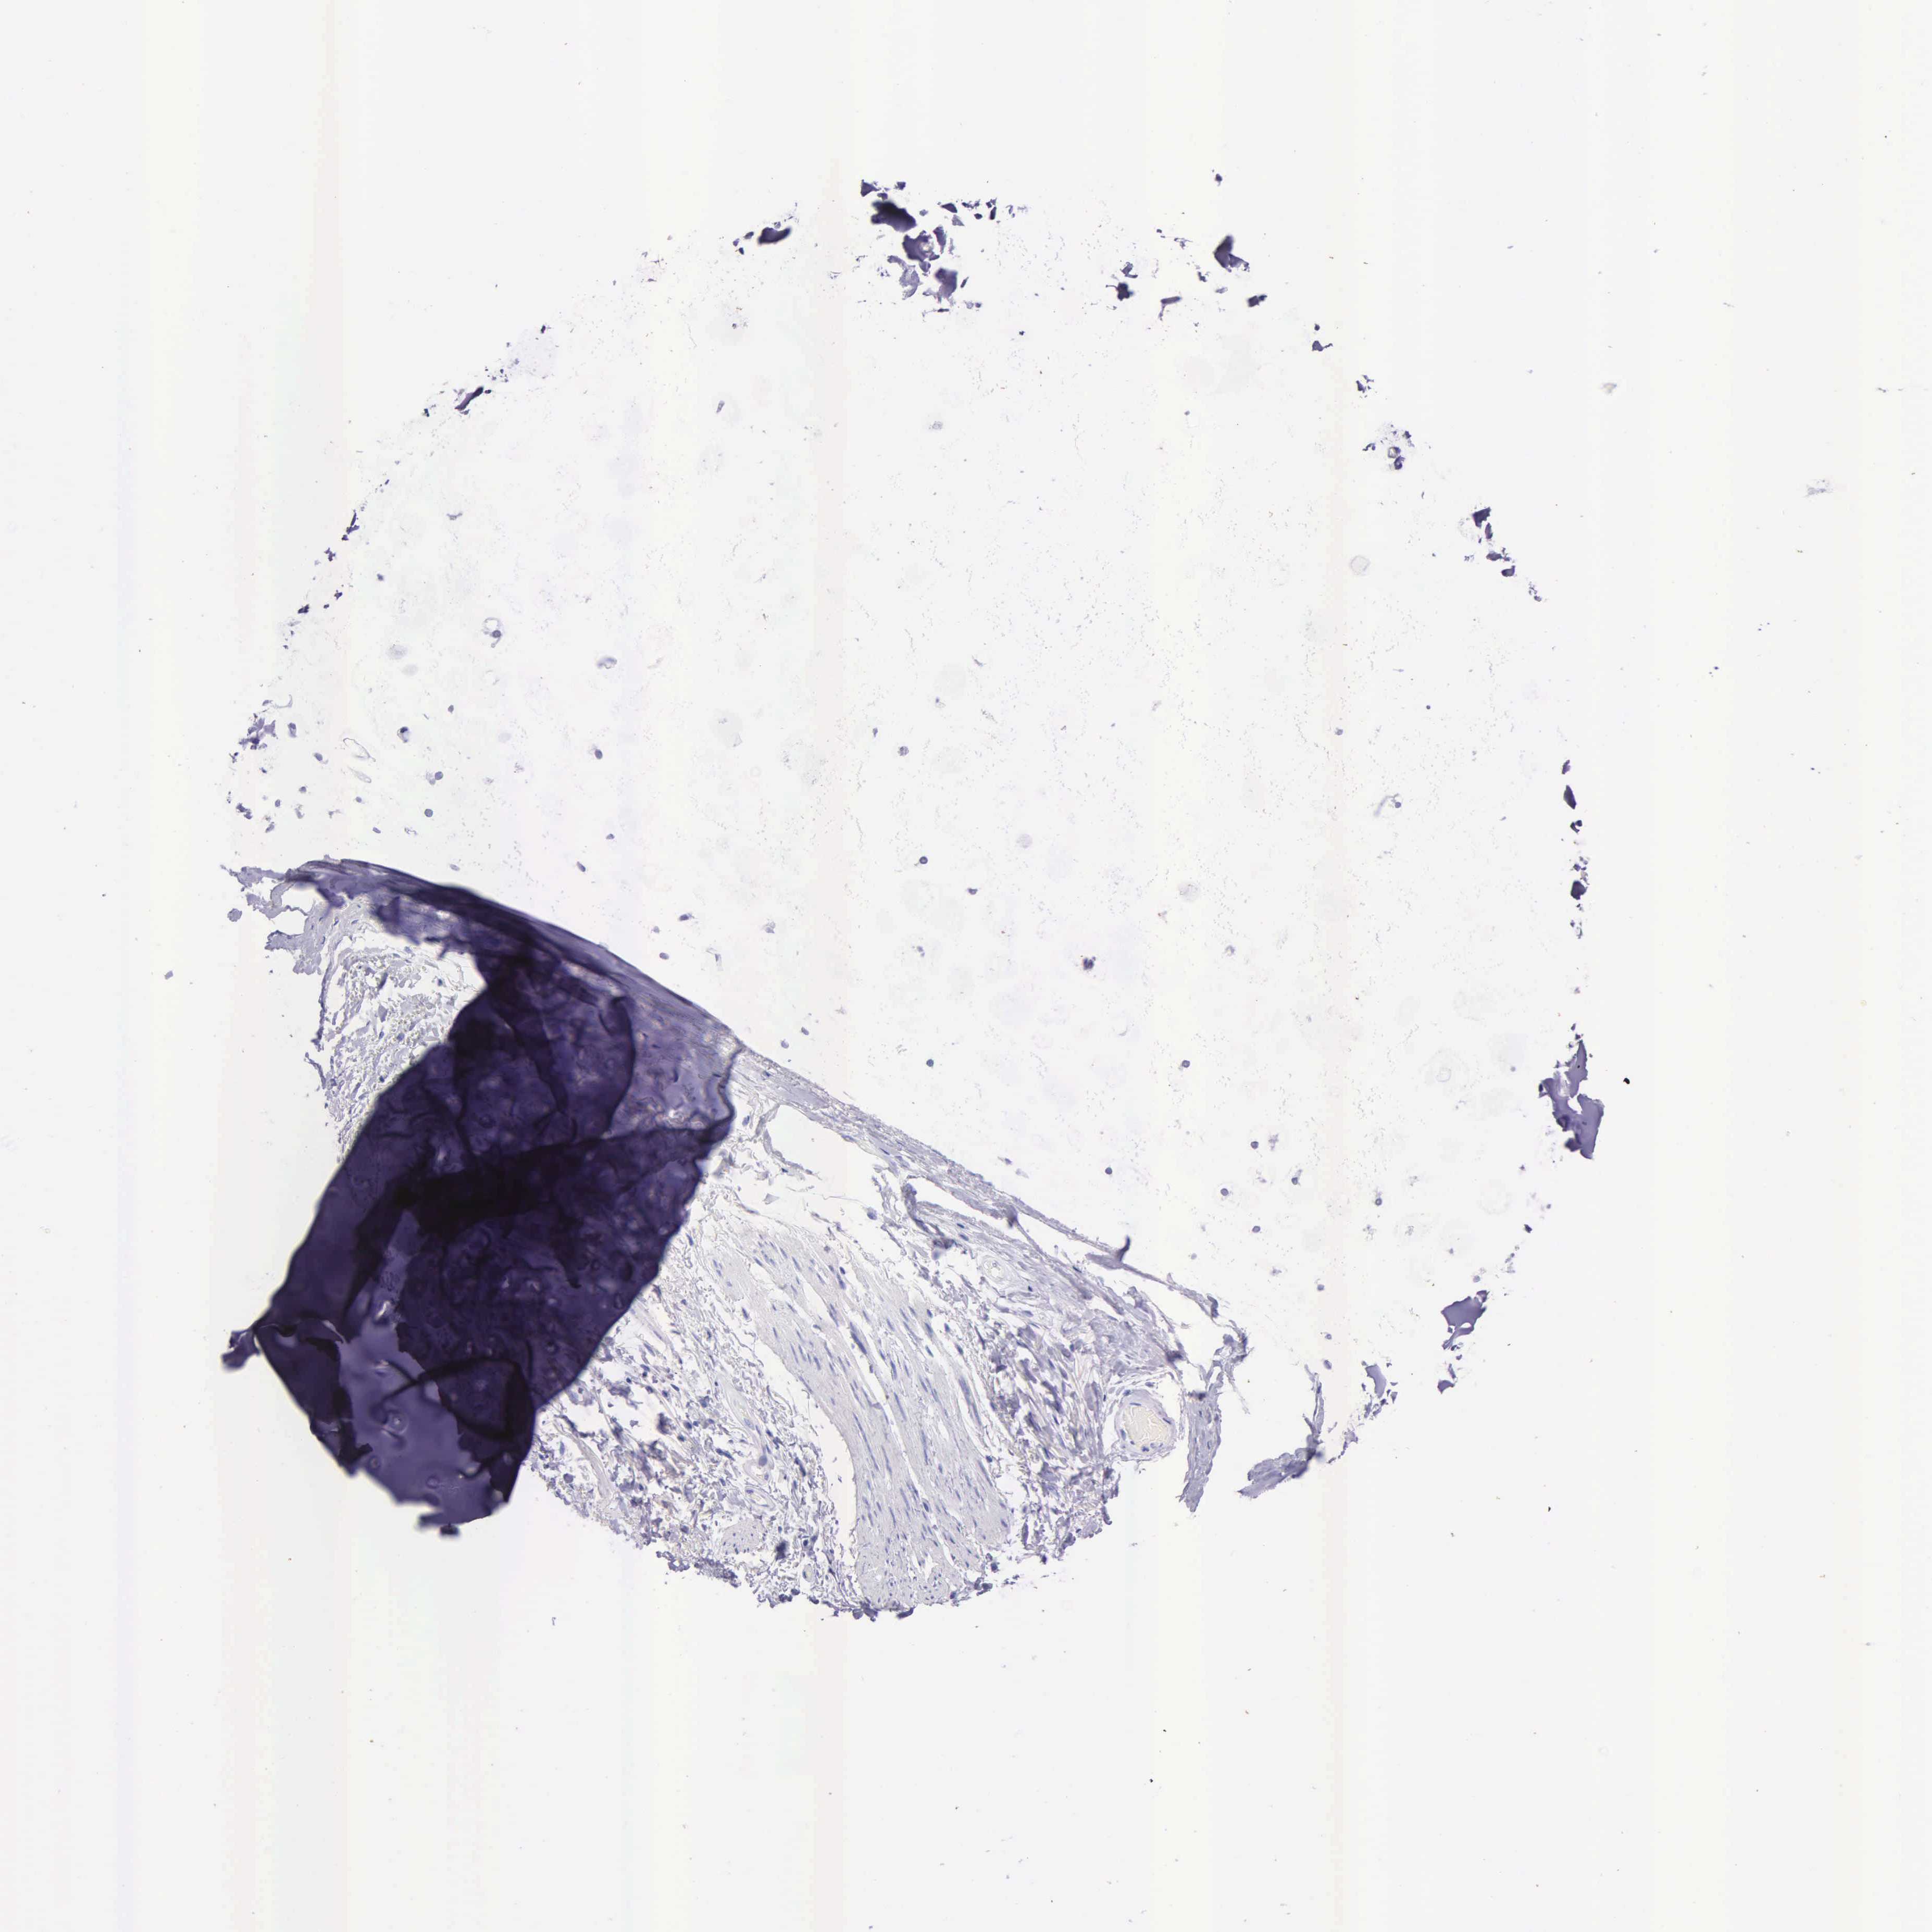

SOFT TISSUE 1 - Antibody stainingi

Antibody staining in the annotated cell types in the current human tissue is reported as not detected, low, medium, or high, based on conventional immunohistochemistry profiling in selected tissues. This score is based on the combination of the staining intensity and fraction of stained cells.

Each image is clickable and will lead to virtual microscopy that enables deeper exploration of all samples and also displays staining intensity scores, fraction scores and subcellular localization as well as patient and tissue information for each sample.

Antibody HPA000764Antibody CAB000070

Chondrocytes Not detected-

Fibroblasts Not detectedNot detected

Peripheral nerve Not detected-